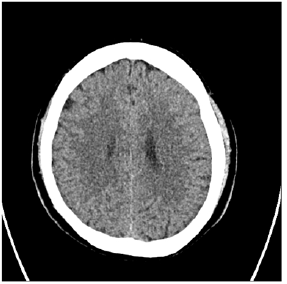

Figure 3: Follow up CT at 6 months post-op showed total resolution of residual CSDH.

The age range was from 20 to 90 years with mean age of 66.5 years (Table 1). There were 122 (70.5%) males and 51 (29.5%) females. Clinically, headache was found in 83 (47.9%), hemiparesis in 141 (81.5%). There were 85 (49.1%) of patients who had the right side, 65 (37.6%) in the left side, and 23 (13.3%) in bilateral CSDH (Table 1). Radiologic follow-up showed removal of the CSDH in all cases with minimum residual in the early postoperative period and complete resolution at late follow-up. All patients were showed good clinical outcomes comparing preoperative period. Mean post-op hospital stay day was 4.5 days (range 3-8). 19 patients (10.7%) show residual CSDH cannot be drained but follow up study shows complete resolution of the CSDH. No patient required revision and no acute hematoma formation. Illustrative case (residual hematoma) A 84-year-old male patient presented with headache and right-side weakness. Brain CT showed a CSDH with midline shift. We performed burr hole drainage under local anesthesia. Postoperative patient response was good, and the patient’s symptoms was gone. However, f/up CT showed residual CSDH [9-14]. The patient symptom was good, so we wait and f/up the patient. The patient symptom was consistently good, so we did not perform further treatment and after 6months f/up CT showed total resolution of residual CSDH (Figures 1-3).